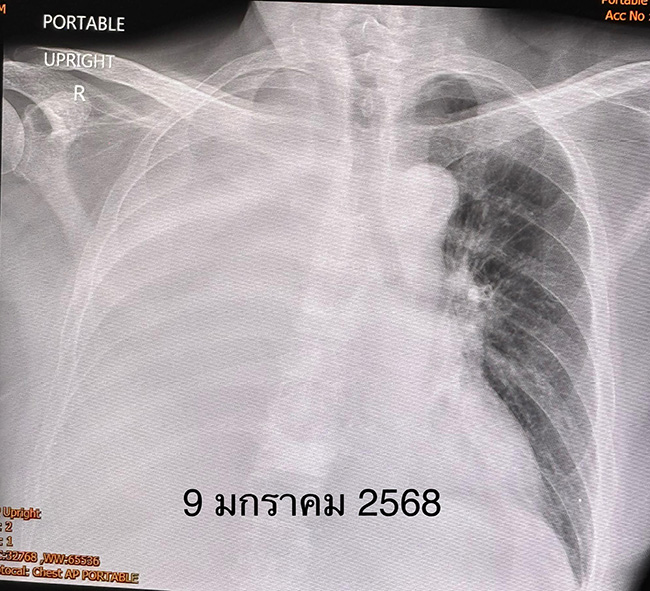

เดือนธันวาคม 2567 เริ่มเหนื่อย มะเร็งกระจายเข้าเยื่อหุ้มปอดข้างขวา ทำให้เกิดน้ำในช่องเยื่อหุ้มปอดข้างขวา ต้องเจาะระบายน้ำ 3 ครั้ง แต่น้ำก็กลับมาอีก เอกซเรย์ปอดข้างขวาขาวทั้งข้าง เข้านอนโรงพยาบาลเพื่อใส่ท่อระบายน้ำจากช่องเยื่อหุ้มปอดด้านขวา และฉีดแป้ง talc ซึ่งประกอบด้วย magnesium silicate ผสมน้ำเกลือเข้าในโพรงเยื่อหุ้มปอด (talc pleurodesis)

หลังฉีดแป้ง ไม่มีผลข้างเคียง น้ำในช่องเยื่อหุ้มปอดลดลง สามารถถอดท่อระบายน้ำออกภายใน 7 วัน ให้กลับบ้านได้ ผู้ป่วยรายนี้เป็นมะเร็งปอดระยะสุดท้าย ให้ยาลดการปวดและทรมาน